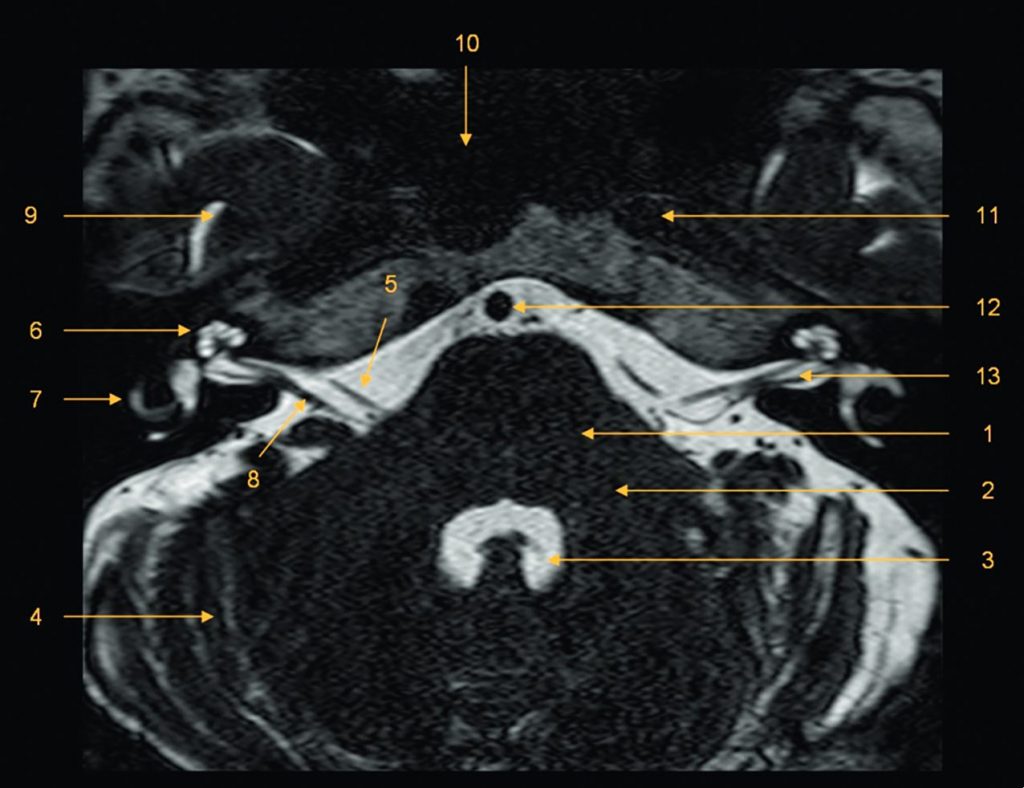

Fig. 62.1 Méat acoustique interne et angle pontocérébelleux : IRM, séquence en écho de gradient à l’état d’équilibre (liquide en hypersignal).

1. Pont. 2. Pédoncule cérébelleux moyen. 3. Quatrième ventricule. 4. Hémisphère cérébelleux. 5. Nerf facial (VII). 6. Cochlée. 7. Conduit semi-circulaire latéral. 8. Nerf cochléovestibulaire (VIII). 9. Lobe temporal. 10. Sinus sphénoïdal. 11. Carotide interne. 12. Artère basilaire. 13. Méat acoustique interne.

Source : CERF, CNEBMN, 2022.